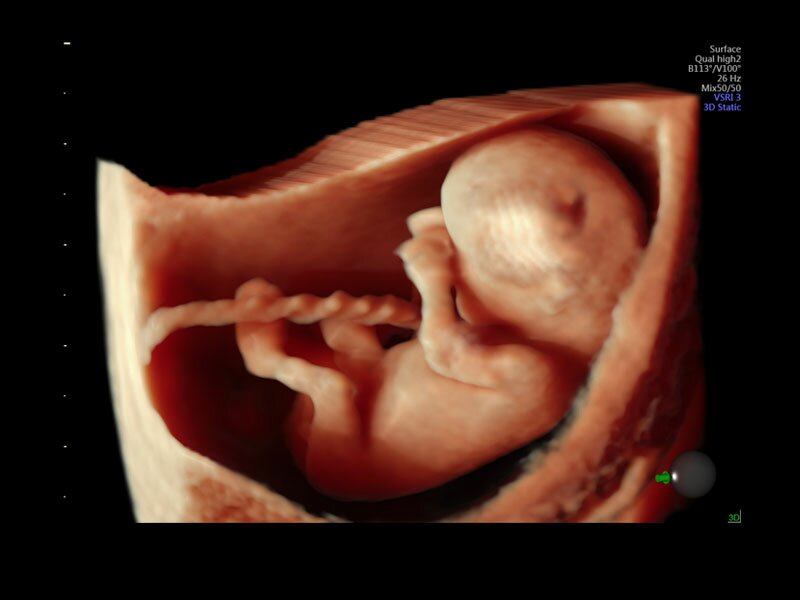

• Программа объемной визуализации плода классический HD-Live + расширенный пакет Hdlive Silhouette и Studio:

• HDlive Silhouette - режим "Силуэт" с подчеркиванием границ тканей и объектов, "объем в объеме"

• Автоматическое определение плода в режиме 3D (SonoRenderLive) – позволяет значительно экономить время и получать изображение конечностей и лица плода в режимах 3D без артефактов и помех – система автоматически определяет границы конечностей и лица плода и выстраивает объемное изображение

Voluson E10 поддерживает инновационные технологии формирования изображений — HDlive Silhouette и HDlive Flow, которые позволяют увидеть мельчайшие детали. Алгоритм SonoRenderlive упрощает рабочий процесс и дает возможность реконструировать изображение поверхностей, определяя область перехода между тканью и жидкостью.

Инновационная технология визуализации HDlive обеспечивает получение реалистических изображений за счет эффекта объемного зрения, повышая достоверность клинической оценки. Теперь режим HDlive дополняют две новые функции:

• Технология HDlive Silhouette — задает разный уровень прозрачности, помогая выявлять контуры внутренних структур и точнее оценивать состояние плода в первом триместре.